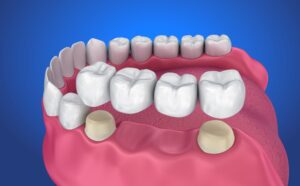

ブリッジやインプラントとの比較

歯を1本失った場合、両脇の歯を削ってつなぐ「ブリッジ」という方法があります。ブリッジはリジッドサポートの考えに近く、違和感なく噛めることが多いですが、何本も歯を失ってブリッジが長くなると、支えている歯に問題が起きた際にまとめて作り直す必要があるというリスクがあります。